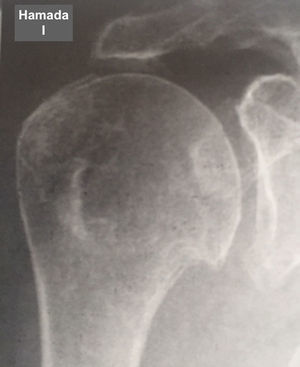

Fue elaborada por Hamada (tabla 6 y figs. 7–11) para describir el tipo de artropatía en roturas masivas del manguito de los rotadores. Utiliza la radiografía convencional y las características de la articulación glenohumeral y el ascenso de la cabeza del húmero para determinar el grado de la lesión. Muestra una correlación quirúrgica y radiológica de cerca del 80%10.